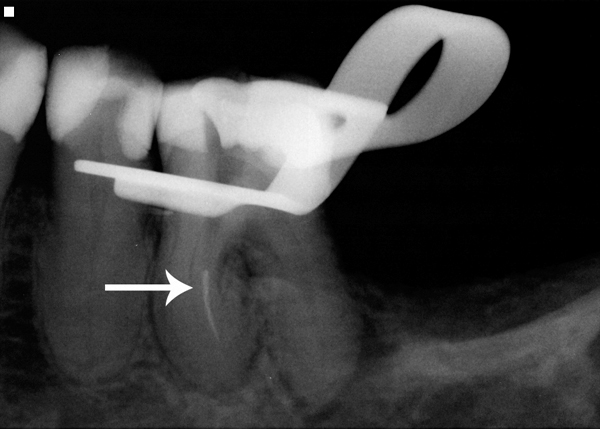

Fig 4. Radiographic example of a separated endodontic rotary NiTi file.

Figure 4

Even with the best preventive measures, endodontic rotary files can still separate within a canal (Figure 4). Although there are many file removal systems on the market today, the chance of successfully removing a broken file depends mainly on where it is located within a canal and the canal morphology. A study by Shen showed that the removal of a fractured NiTi instrument is more influenced by tooth anatomy, degree of root canal curvature, and fragment location than a specific technique.10 A study by Souter concluded that the limited success of file removal, increased risk of perforation, and reduced root strength suggest that file removal beyond the curved portion of the root should not be routinely attempted.11